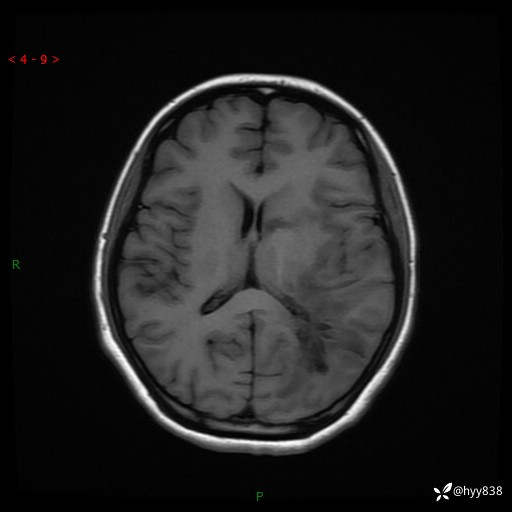

颅脑MRI平扫+增强